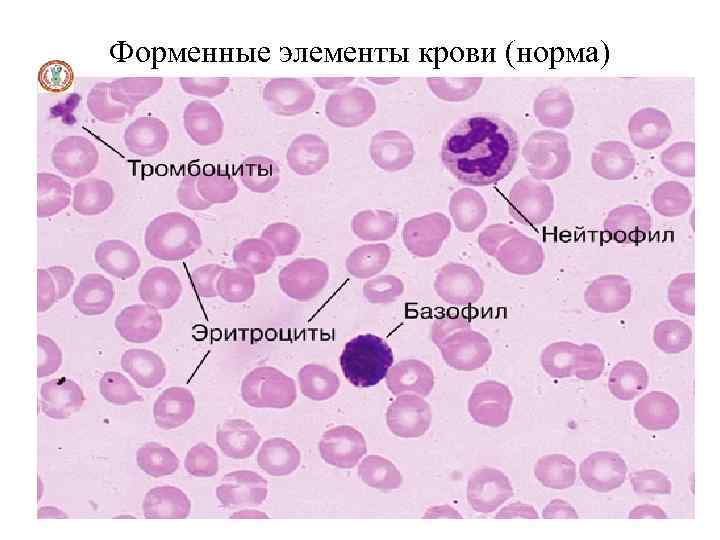

Форменные элементы крови (норма)

Что Вы видите на слайде?